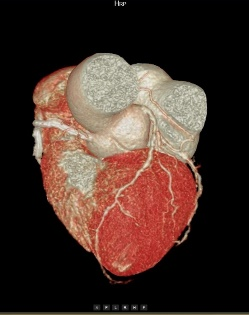

心血管成像能力方面目前

业内最好

面对高心率达到200bpm的患者,心律高度不齐、房颤、房扑的患者,都能够呈现清晰的图像质量:

(1)拥有业内最宽的16厘米探测器,轻松应对复杂心率和心律;

(2)拥有业内最全的心脏冠脉成像解决方案。

高心率+高清晰+智能分析

多维度参数评估,精准影像诊断